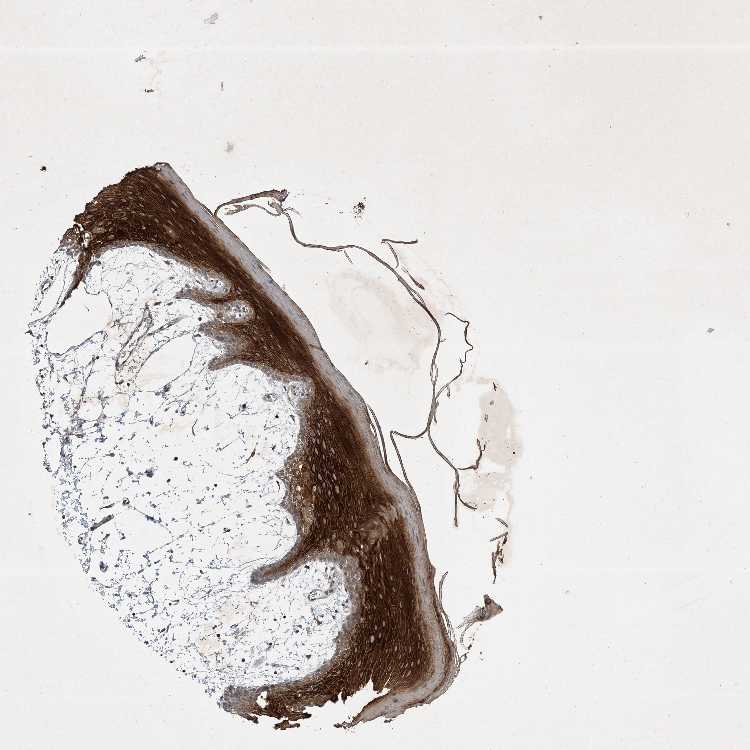

TISSUE PRIMARY DATA ORAL MUCOSA Show tissue menu

Oral mucosa

ORAL MUCOSA - Antibody stainingi

Antibody staining in the annotated cell types in the current human tissue is reported as not detected, low, medium, or high, based on conventional immunohistochemistry profiling in selected tissues. This score is based on the combination of the staining intensity and fraction of stained cells.

Each image is clickable and will lead to virtual microscopy that enables deeper exploration of all samples and also displays staining intensity scores, fraction scores and subcellular localization as well as patient and tissue information for each sample.

Antibody HPA029666Antibody HPA029667Antibody HPA029668Antibody HPA029669

Squamous epithelial cells MediumNot detectedHighHigh